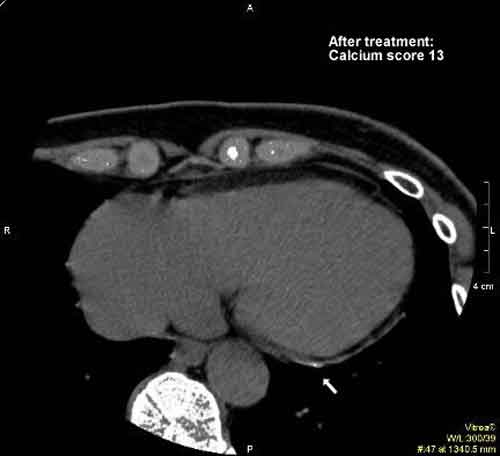

Will The Coronary Calcium Score • 1990:Agatston published standardized protocol for quantification of coronary artery calcium ... Retrieve Content

Szilard Voros - Wikipedia, The Free Encyclopedia